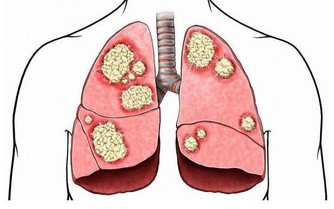

3. 你的腸道裡有寄生蟲

大便中的白色斑點也可能是絛蟲或蟯蟲。雖然如今絛蟲感染並不常見,但依然有可能。如果看到白色或黃色的斑點,可能就是絛蟲,它們通常是扁平的、方形的,大小與米粒相當。有些人可能沒有症狀,但有些人可能出現胃痛或腹瀉。人們通常是因為吃生的或未煮熟的肉而感染絛蟲。絛蟲感染比較好治療,一粒藥丸就足以殺死絛蟲,它會從糞便中排出體外。

大便上出現白點,是什麼原因造成的?

蟯蟲感染更常見,特別是在兒童中。蟯蟲很小,是白色的,大小和訂書針一樣大。

它們通常看起來像白線,所以也被稱為線蟲。

蟯蟲通常生活在腸道的下部,並在肛門周圍的皮膚上產卵,這可能會導致肛門不適和瘙癢。

人們往往是從其他人的大便中被感染蟯蟲卵,

所以去完公共衛生間後徹底洗手,是避免蟯蟲感染的基本常識。

治療蟯蟲的藥物一般分兩次服用,而且家中的每個人都需要治療,以確保他們沒有感染。

另外,要定期清洗衣物和床上用品,以避免再次感染,經常洗手、指甲別留太長,也是重要的防護措施。